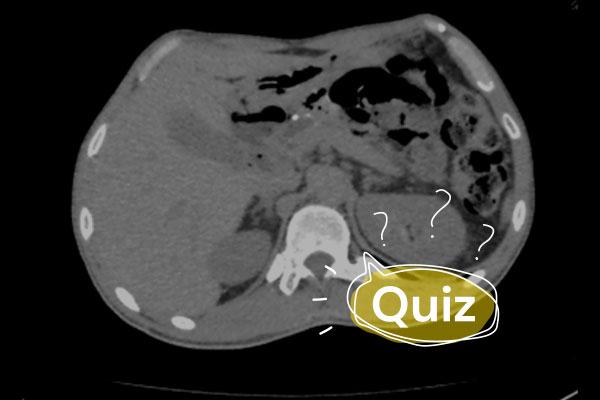

É solicitado um raio-X de tórax:

Com essa imagem, alguns diagnósticos diferenciais foram pensados. Qual o conjunto de exames mais apropriado para melhor avaliação do quadro?